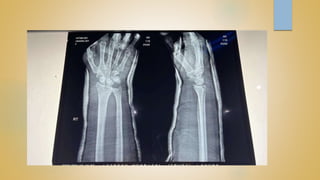

• DISTAL RADIUS FRACTURES ARE THE MOST COMMON

ORTHOPAEDIC INJURY AND GENERALLY RESULT FROM FALL ON AN

OUTSTRETCHED HAND

• DIAGNOSIS IS MADE CLINICALLY AND RADIOGRAPICALLY

RADIOGRAPHIC CRITERIA